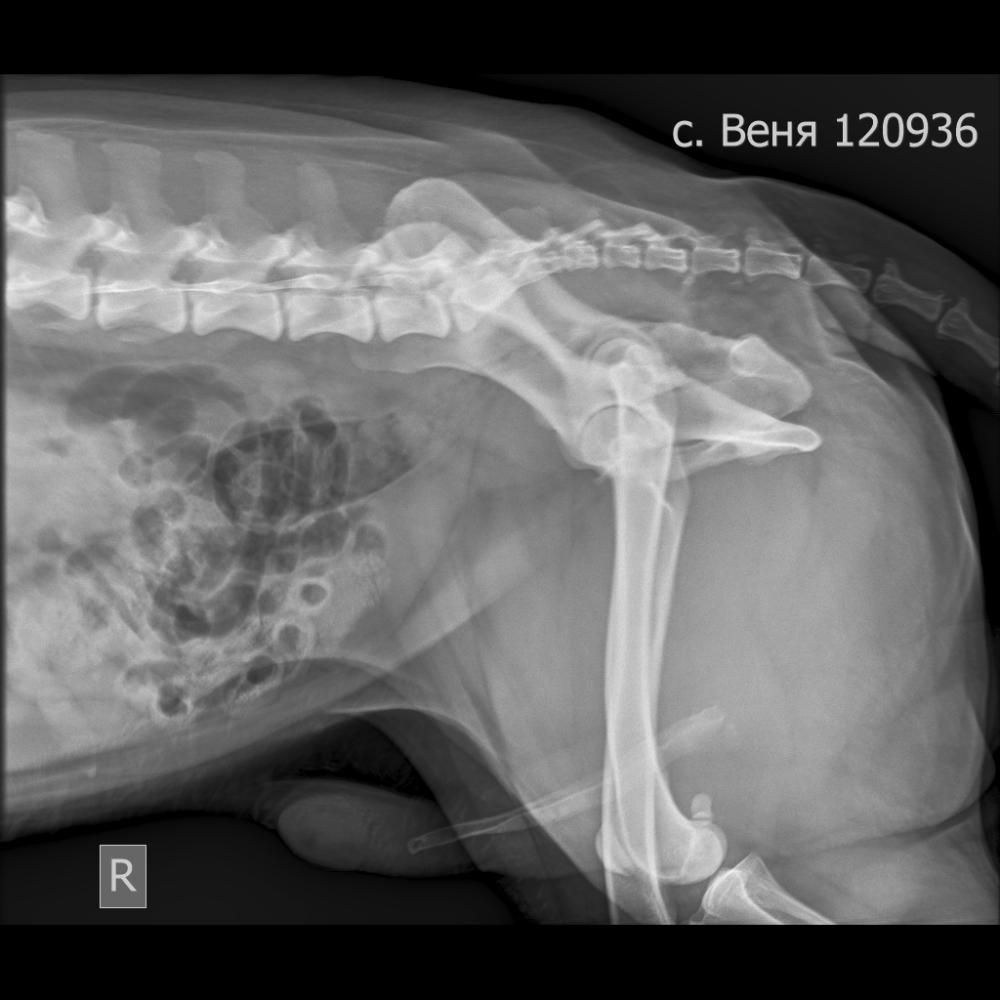

Рентген:

Тени органов видимой части брюшной полости

визуализируются чётко. В видимой части петель

тонкого отдела кишечника определяются

однородные массы и газ. В видимой части толстого

отдела кишечника визуализируются каловые массы

и газ. Не выявлено признаков механической

непроходимости видимого участка ЖКТ на момент

исследования. Стоит учитывать возможность

наличия неконтрастных инородных предметов,

которые невидимы на рентгенограммах. Видимая

часть селезёнки визуально без отклонений. Тени

почек вне зоны коллимации. Не выявлено

изменений в области проекции мочеточников.

Мочевой пузырь наполнен, в его проекции

визуализируются множественные дополнительные

тени повышенной рг-плотности - уролиты,

минерализованный осадок. Простатомегалия. В

суперимпозиции с средней третью половой кости

визуализируются две дополнительные округлые

тени повышенной рг-плотности - уролиты в уретре.

Описанные находки не исключают наличие

уратных, цистеиновых и прочих

нерентгеноконтрастных включений. Объёмные

образования в видимой части брюшной полости не

выявлены, что не исключает наличие образований с

низкой рентгенологической плотностью и низким

масс-эффектом, а также наличие образований вне

зоны коллимации. Поверхностные ткани без

рентгенографических отклонений. Все костные

структуры соответствуют породе и возрасту.

Более значимых находок не выявлено. Учитывайте

чувствительность и специфичность данного метода

исследования. В ходе интерпретации

рентгеновских снимков были описаны

предварительные диагнозы, которые объясняют

находки на снимках. Диагноз не является

окончательным и должен быть интерпретирован

лечащим врачом на основании клинических и

анамнестических данных.